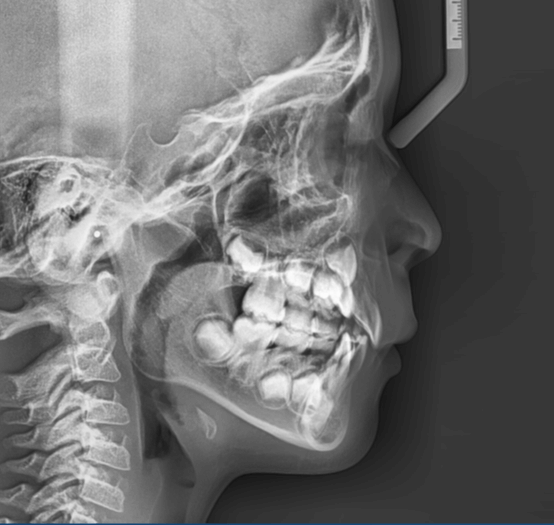

| 年齢・性別 | 11歳1ヶ月の女性 |

|---|---|

| 主訴 | 口元の突出感と歯並びが気になり、将来的な咬合状態を整える目的で来院された患者様です。 |

| 治療期間・回数 | 2年6ヶ月・25回 |

| 費用 | 720,000円 |